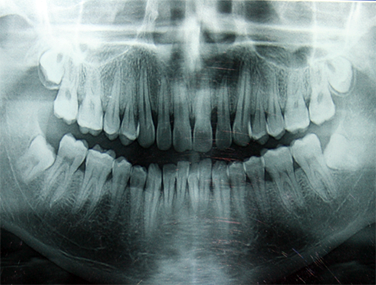

OPG (Orthopantomogram)

An OPG is a Panoramic or wide view x-ray of the lower face, which displays all the teeth of the upper & lower jaw on a single film. It demonstrates the number, position & growth of all the teeth including those that have not yet surfaced or erupted.

It also reveals problems with jaw bone and the joint which connects the jaw bone.